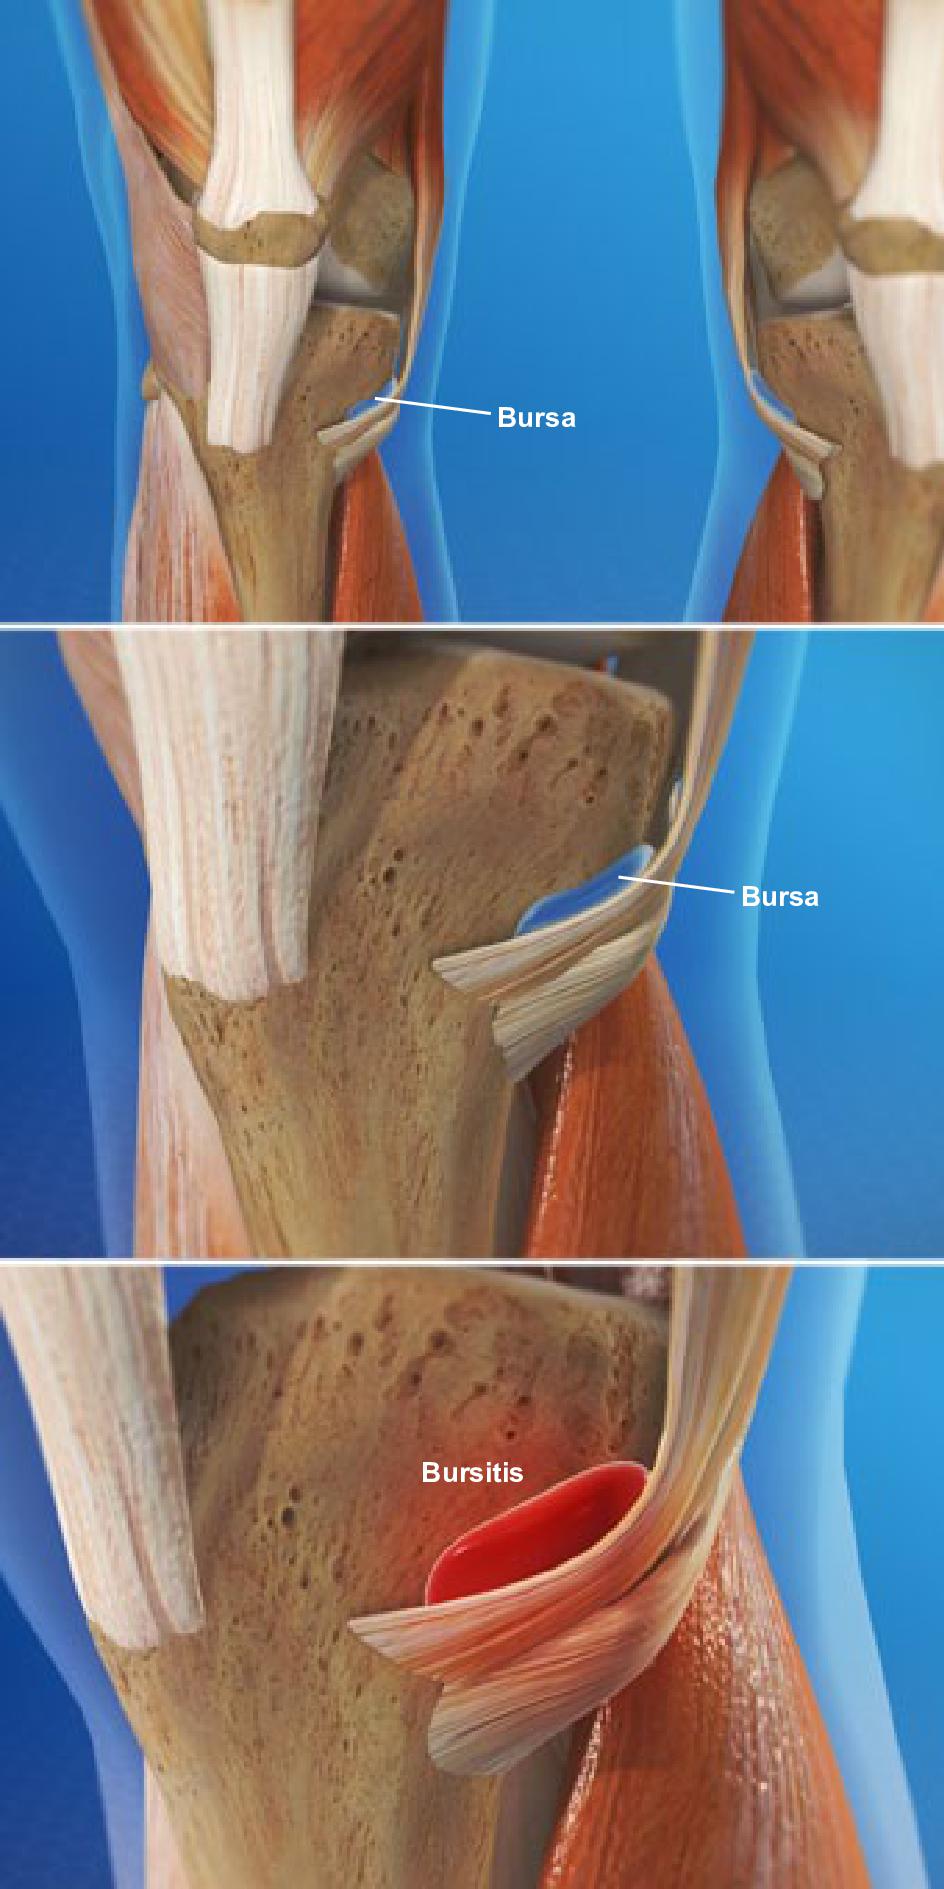

Заболевание сустава: симптомы и лечение

Раздел: Фотодневник открытий